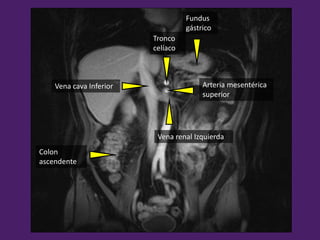

Fundus

gástrico

Vena renal Izquierda

Arteria mesentérica

superior

Tronco

celíaco

Vena cava Inferior

Colon

ascendente